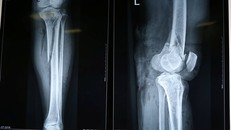

Bất cẩn trong lúc tham gia giao thông, bệnh nhân L.T.P đã bị tai nạn giao thông khiến gãy chân và tổn thương mạch máu phải nhập viện cấp cứu.

Nạn nhân bình tĩnh gọi điện thoại dù bị gãy gập chân

Bị TNGT gãy chân, cô gái nén đau nằm giữa đường gọi điện thoại

(Ngày Nay) - Vụ va chạm giao thông khiến đối nam nữ ngã văng ra đường, nam thanh niên nằm bất tỉnh tại chỗ, cô gái ngồi sau bị gãy gập chân trái vẫn bình tĩnh nằm tại chỗ bấm điện thoại cho người thân.